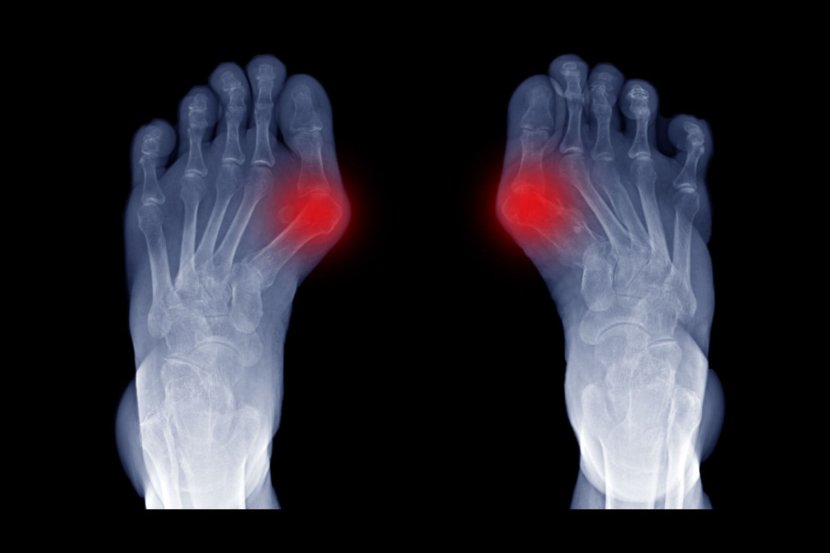

Osnovna razlika između kurjeg oka i čuklja (hallux valgus) jeste u tome što je čukalj unutrašnja struktura (promena.) Za razliku od kurjeg oka, nije kožna, već koštana. Čukljevi izgledaju kao kvrge koje "izlaze" (nastavljaju se) najčešće iz malog prsta na nozi ili podnožja palca (metarzofalangealni zglob). Njihova međusobna uzročno-posledična veza je u tome što čukljevi mogu da prouzrokuju veće trenje o obuću, čime se otvaraju mogućnosti i za pojavu kurjeg oka.

Čukalj nastaje kada prst ispada iz uobičajenog ležišta. Zglob postaje veći i i onda štrči izvan stopala kao kvrga. Oko tog dela koža može da bude i sasvim normalna, ali i sa otokom i crvenilom.Uzroci nastanka su različiti, od genetske predispozicije, artritisa ili loših životnih navika i neadekvatnog izbora obuće.

• kvrgava koštana izraslina u osnovi nožnog palca, korenu malog prsta ili na peti

• promenjeni položaj i iskrivljenje nožnog palca ka unutrašnjoj strani stopala

• pojačana osetljivost, crvenilo ili otok oko izrasline

• ograničeni opseg pokreta stopala

Kada se javi na peti, u pitanju je zadnji deo stopala, kod Ahilove tetive (Haglundov deformitet). Uzrok je pritisak na zadnji deo pete zbog tesne ili neudobne obuće. Uz sam čukalj, javljaju se još i otok u predelu Ahilove tetive, bol, upala tog dela i crvenilo.